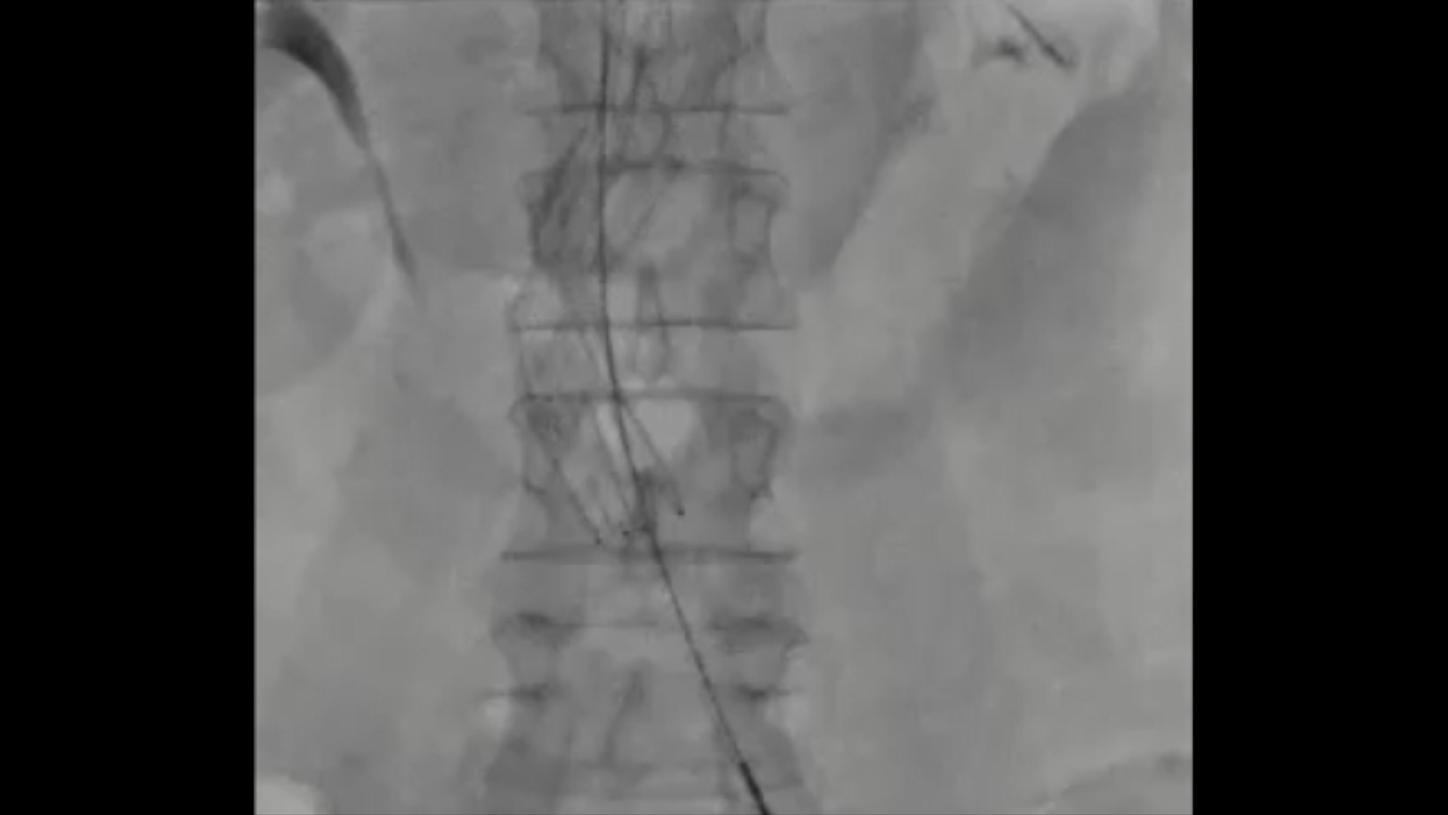

Iliosacral Screw Fixation, Spinal Fusion

syngo DynaCT Large Volume and syngo DynaCT 360 can visualize large anatomical areas

- Spine: Height of up to 23.5 cm (9.3”)

Clinical images courtesy of University Hospital Ulm, Germany (left) and Jikei University, Tokyo, Japan (right).